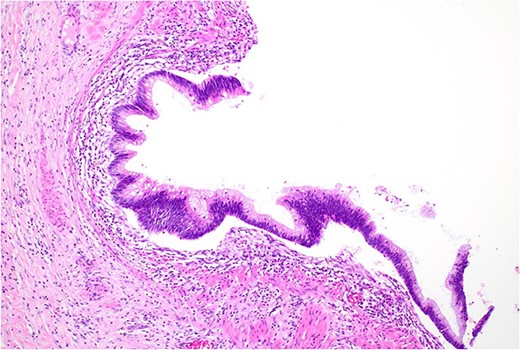

Histopathology macroscopically identified a 42-mm cystic caecal mass adjacent to the ileocaecal valve (Figs 4–5). Microscopic examination revealed a duplication cyst involving the ileal and colonic tissue comprised of a complete duplication of the colonic wall including mucosa, submucosa and muscularis propria, which was shared with the involved colon (Fig. 6). There was no mucosal connection to adjacent normal bowel. There was some ulceration with inflammatory changes in the overlying mucosa suggestive of prior cyst perforation and areas of attenuated villiform mucinous epithelium with features of low grade dysplasia (Figs 7-8). Special stains for organisms (Periodic Acid-Schiff (PAS), Fredericamycin A (FMA), Ziehl-Neelsen (ZN) and modified ZN) were negative. There were no granulomas, heterotopic mucosa or evidence of malignancy. Twenty-nine lymph nodes were identified with no evidence of malignancy.

Area of dysplastic mucosa (right) within the duplication cyst that shares a common wall with the right colon (left), low power.

Low grade dysplasia in duplication cyst epithelium, high power.